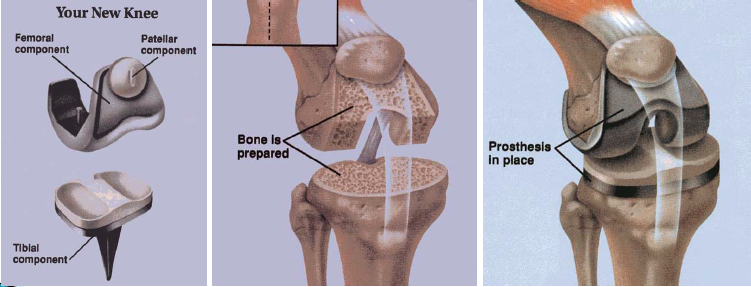

Quelles sont les caractéristiques de la prothèse totale du genou?

De façon similaire, la prothèse totale du genou représente le traitement de choix pour l’arthrose du genou. La popularité de cette procédure a également augmenté de façon exponentielle au cours des dernières années, si bien qu’elle est maintenant pratiquée plus fréquemment que les arthroplasties de hanche.

Il faut savoir que la réhabilitation d’une prothèse totale du genou est nettement plus difficile que pour une prothèse totale de hanche. Les facteurs de risques pour la gonarthrose sont similaires à ceux de la hanche et comprennent :

Les études démontrent une survie à 90 % à dix ans pour des prothèses totales du genou. Les complications usuelles reliées à cette procédure sont:

La thrombophlébite demeure la complication la plus fréquente reliée aux prothèses totales de hanches et de genoux, si bien qu’une thromboprophylaxie est indiquée chez tous les patients de façon à prévenir cette complication. Les agents recommandés sont l’héparine de bas poids moléculaire, la warfarine (Coumadin), ou les nouveaux anticoagulants oraux (Xarelto). La durée recommandée de traitement pour une prothèse totale de hanche est de 35 jours et, pour une prothèse totale de genou, de quatorze jours.